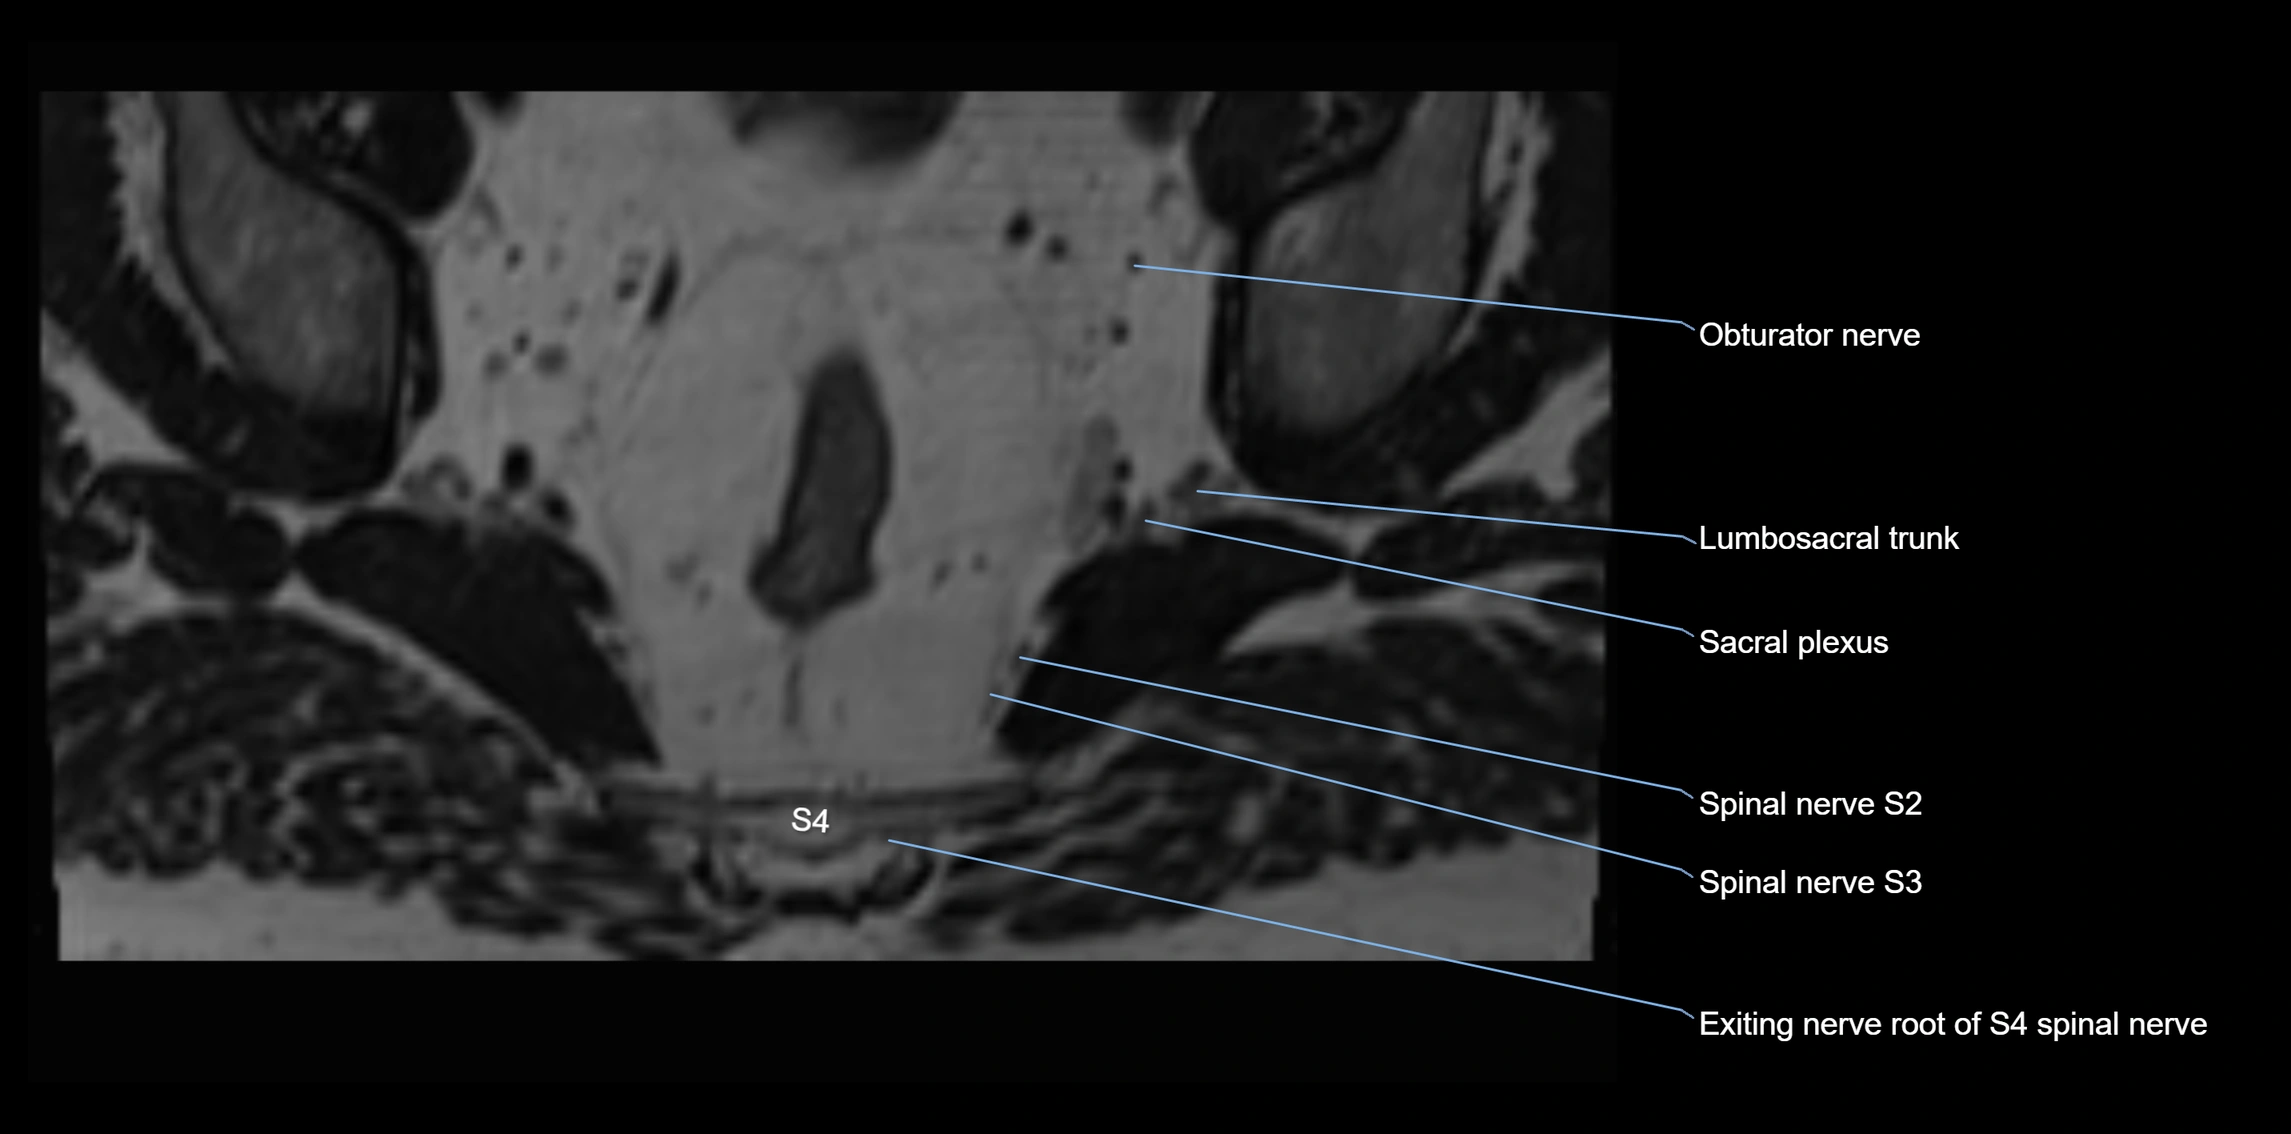

MRI image

image